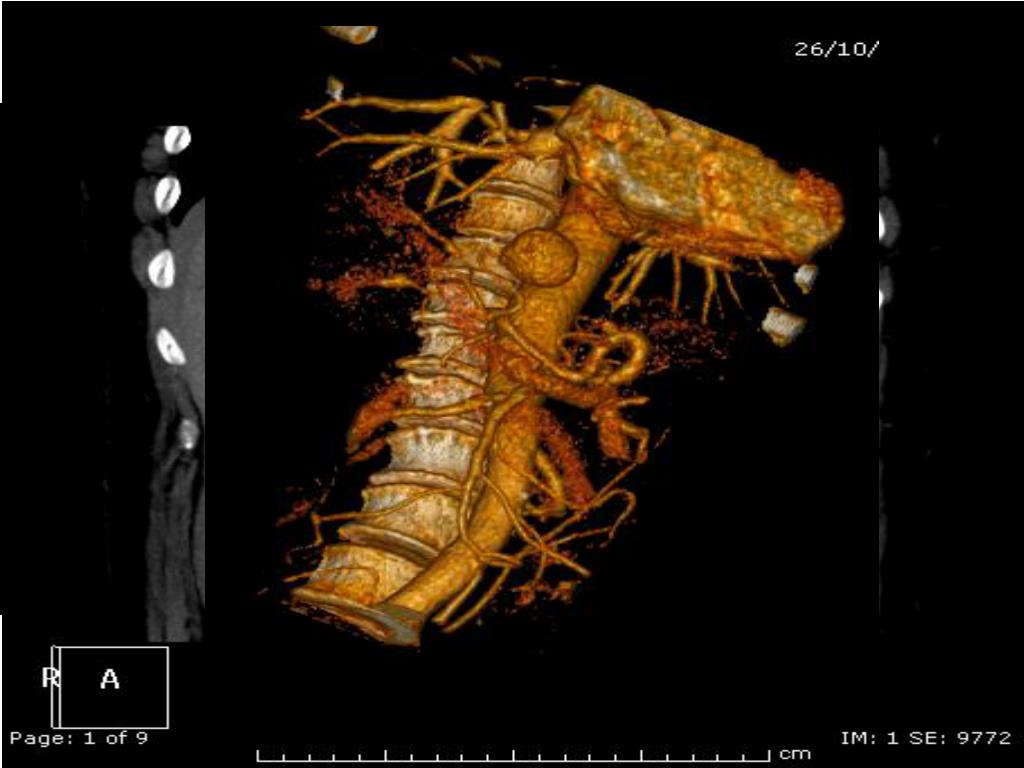

2. G. M. 62 anni donna Anamnesi Epicrisi Colecistectomia VLS Sdr di Sjogren diagnosticata nel 2010 (in terapia corticosteroidea) 23.10 : ricovero per sospetta sepsi da infezione delle vie urinarie (Febbre con brivido, leucocituria) Esami ematochimici all’ingresso Hb: 13,1 g/dL, GB 13000, PCR 190 mg/, ALT 21 U/L Dolori addominali ed anemizzazione Ecoaddome: falda di versamento in tutti i recessi TC addome Francesco E. D’Amico

3. Francesco E. D’Amico

4. Francesco E. D’Amico

5. Francesco E. D’Amico